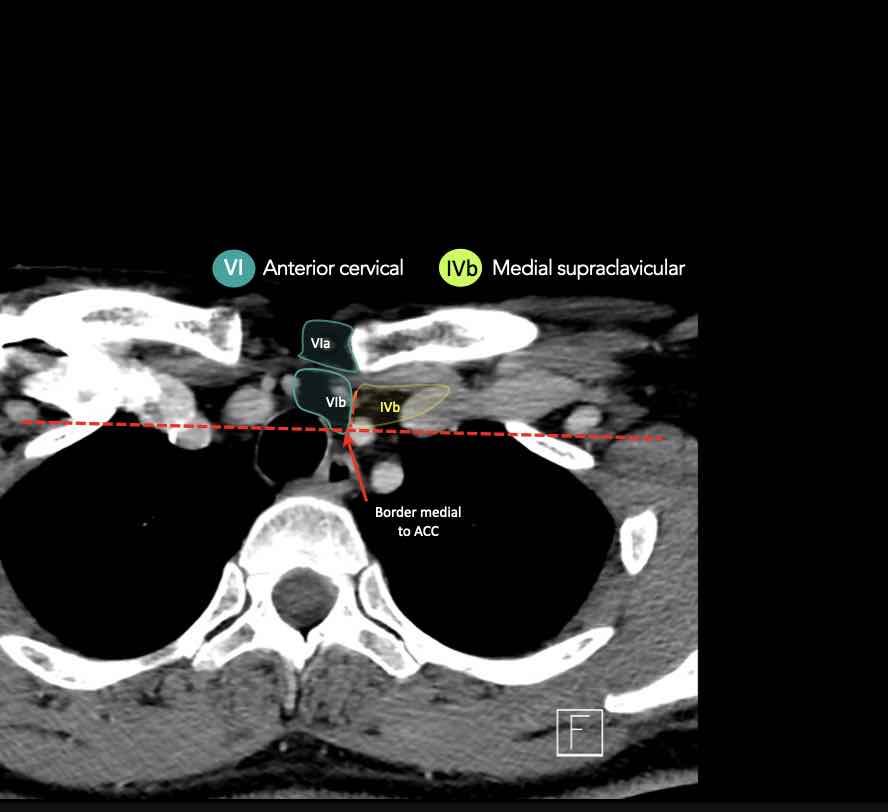

IV – Tĩnh mạch cảnh dưới và hố thượng đòn trong

Ranh giới giữa tầng IVa và IVb được xác định tùy ý tại vị trí 2 cm phía trên khớp ức đòn.

Tầng IVb

Các hạch này có nguy cơ chứa di căn từ các ung thư hạ hầu, thanh quản dưới thanh môn, khí quản, tuyến giáp và thực quản cổ.

VI – Cổ trước

Tầng này chứa các hạch tĩnh mạch cảnh trước nông (tầng VIa) và các hạch sâu hơn bao gồm hạch trước thanh quản, trước khí quản, cạnh khí quản và hạch thần kinh thanh quản quặt ngược (tầng VIb).